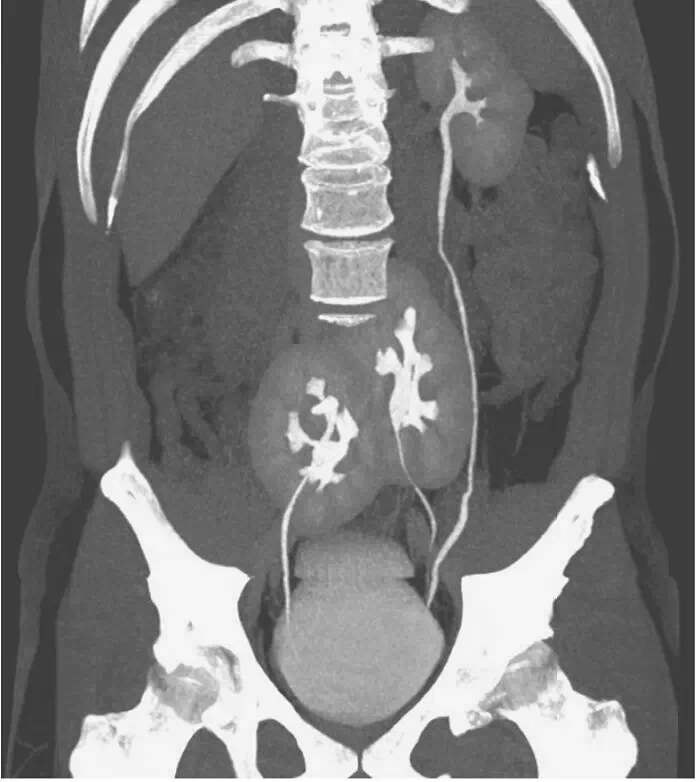

Trois reins découverts chez un homme

Un homme de 38 ans se présente en 2020, suite à d'intenses douleurs lombaires, à l'hôpital de Rim, à São Paulo (Brésil). Les médecins découvrent alors que l'homme est pourvu de trois reins, au lieu de deux. Le rein gauche est à son emplacement normal, mais il est accompagné de deux reins qui ont fusionné au centre du pelvis.